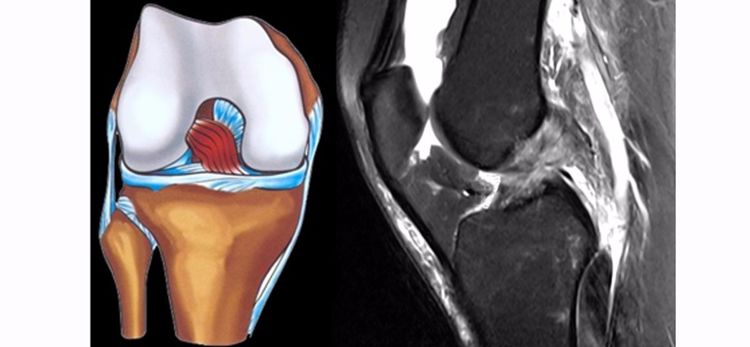

ACL损伤的MRI分级——

Grade1:韧带内损伤,无长度改变。

Grade2:韧带内损伤并长度延长。

Grade3:完全性韧带撕裂。

Grade1、2级为韧带的部分损伤,Grade3级为韧带的完全断裂。

ACL最好的观察层面:最好的观察层面是斜矢状面,同时需要结合横断面和冠状面。